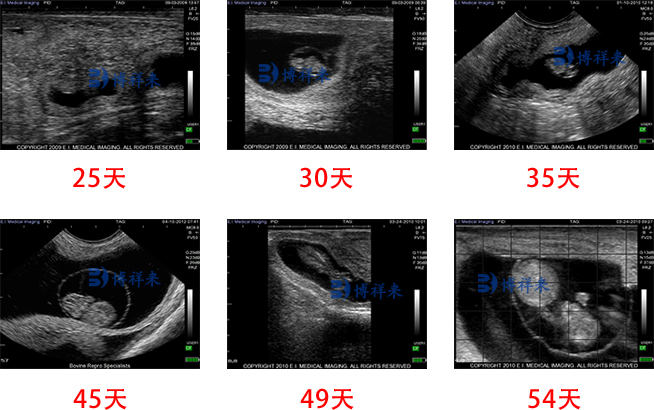

首先,牛用B超机具有非侵入性检查的特点,不需要插入任何工具或物质,对母牛没有任何伤害。它采用高分辨率的B超技术,能够清晰显示胎儿的结构和发育情况。通过观察B超图像,您可以准确判断牛的胎龄,从而做出相应的管理决策。

其次,牛用B超机具备实时性,可以立即显示图像,帮助您实时观察胎儿的运动和发育情况。一次检查就能获取较为全面的信息,让您对牛胎龄有更清晰的了解。